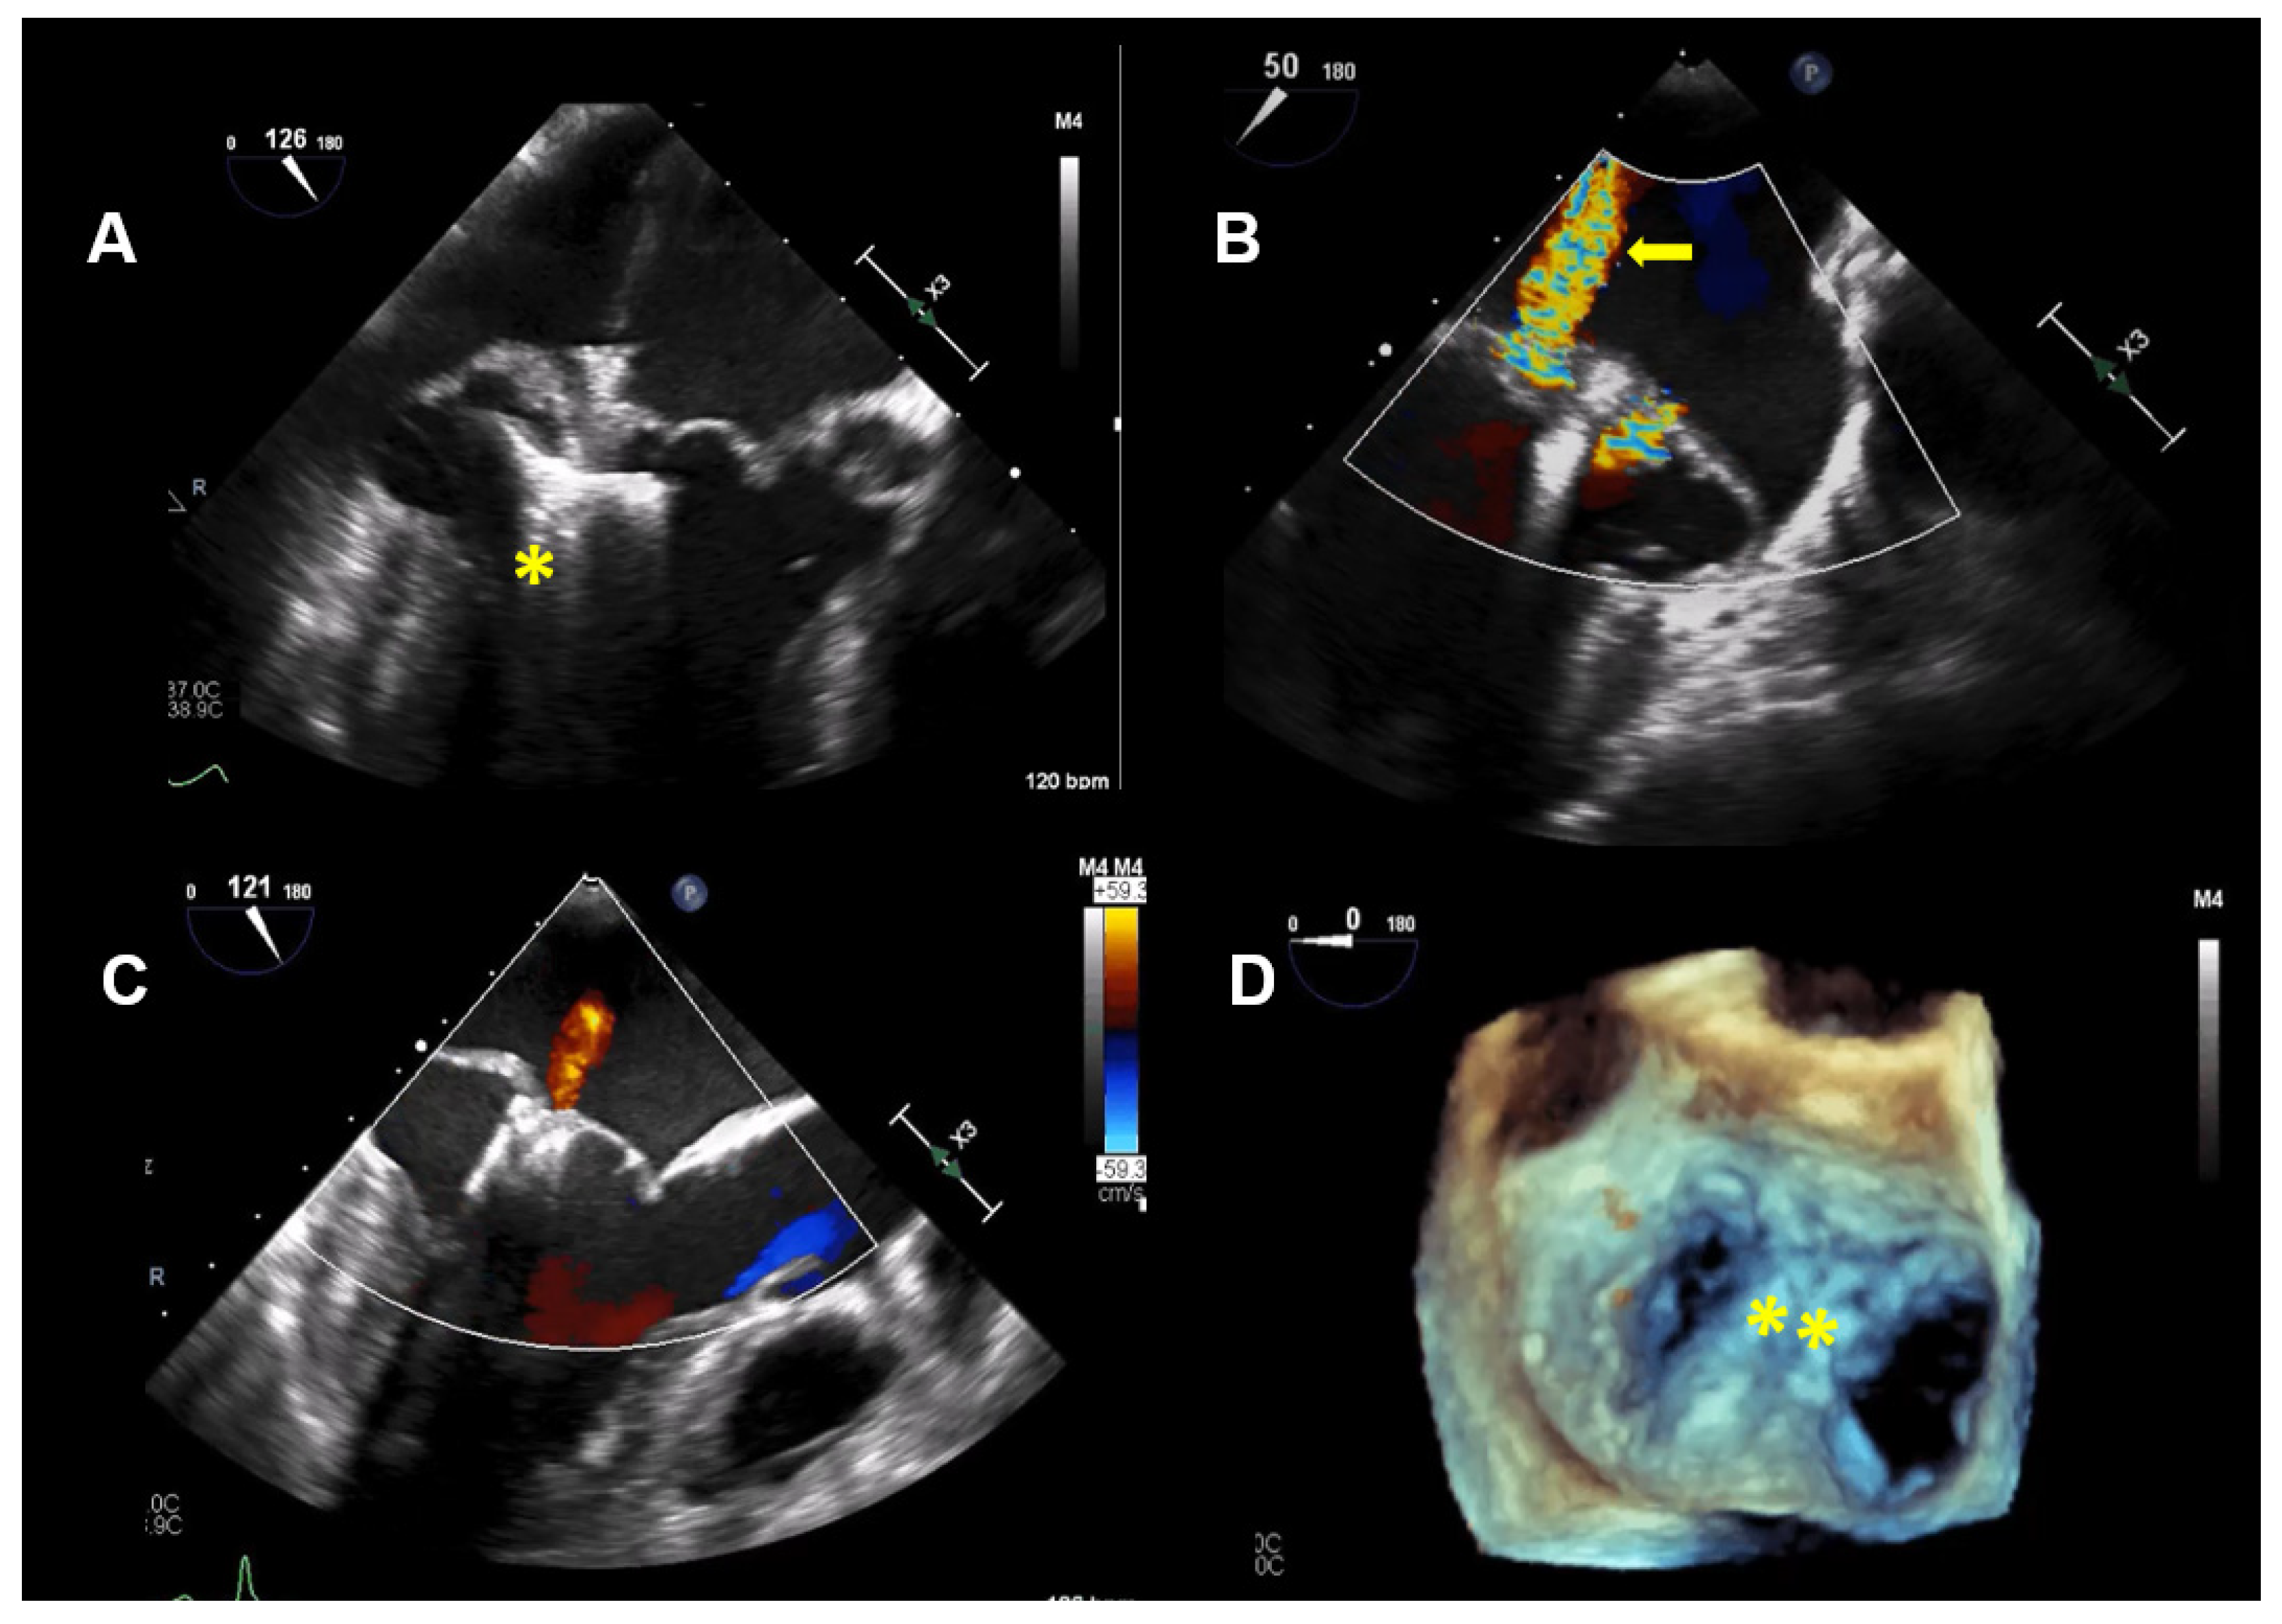

Thus, based on all of the findings, an increased perioperative morbidity in this MR patient was hypothesized and, also, to comply with the patient not wanting surgery, the decision was made to proceed with a percutaneous MV repair strategy. Subsequently, two MitraClips (XTR) (Abbott Vascular, North Chicago, Illinois, USA) were implanted with an excellent result, with minimal residual MR (Figure 4). One year after MitraClip implantation, the patient reported significantly fewer palpitations, and her exercise tolerance was normal. TTE imaging documented normal LV function with a LVEF of 60%, normal pulmonary artery systolic pressure and mild, late-systolic MR. Using Zio XT patch monitoring, a marked reduction in PVCs from 18.7% to 1.2% and rare SVT were seen, and no nsVT occurred (data are in Figure 5).

Figure 4.

Case 2: Procedural transesophageal echocardiographic imaging during MitraClip XTR (Abbott Vascular, North Chicago, Illinois, USA) implantation. (A) The first MitraClip XTR (yellow asterisk) is positioned below the mitral leaflets with opened Clip arms. (B) Residual mitral regurgitation (MR) after implantation of the first Clip is marked with a yellow arrow. (C) After positioning of the second Clip, only mild MR is present. (D) The 2 MitraClip XTR devices (yellow asterisk), which create a double orifice, are seen in a 3D enfaced view.